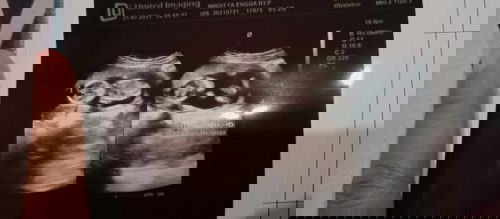

Apakah bayi berkembang sempurna ?

Mau tanya, hasil usg saya ini bayinya berkembang sempurna tdk ya? Karena dokter tidk menjelaskan apa", dan saya tidak bisa menganalisa usg